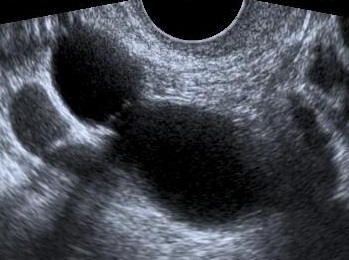

The presence of an incomplete septum in an anechoic mass with smooth tubular shape and poor vascularization facilitates discrimination between hydrosalpinx and other adnexal masses. Additionally, a history of previous abdominal operations or infections further supports the diagnosis of hydrosalpinx (Domali E. et al, 2007).